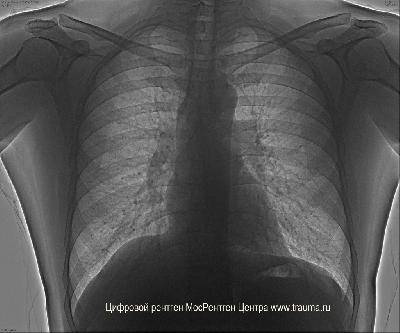

М 1982 г. р., толщина зоны интереса 18 см. Режим 100 кВ, 1 мАс, задне-передняя проекция.При рентгене грудной клетки у курильщика хорошо видна трахня и главные бронхи, что может быть связано с постоянным воспалением дыхательных путей, которые раздражает табачный дым.

Так как у пациента еще болела спина, он не смог в достаточной мере охватить детектор и поэтому лопатки оказались видны, мешая рассмотреть легочные поля. Если бы это знать заранее, нужно было бы поставить режим 2 мАс.

Проекции исследования: прямая проекция.

Положение пациента: сидя.

ЭЭД: 0.2 мЗв.

Качество снимков: удовлетворительное.

Легочные поля: без инфильтративных и очаговых изменений.

Легочный рисунок: не изменен.

Корни легких: не расширены, структурны.

Синусы: свободны.

Плевральная полость: газ не определяется.

Апикальная плевра: не изменена.

Междолевая плевра: не изменена.

Диафрагма: обычно расположена.

Сердце: без заметного увеличения отделов.

Аорта: без особенностей.

Тень средостения: не расширена, не смещена.

Контуры трахеи и бронхов усилены.

Костная система: костно-травматических изменений нет.

Заключение: Хронический бронхит?